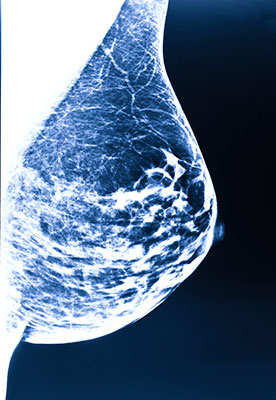

“If she has the mutation, we know how to deal with that,” said Dr. Warner, noting that women who carry either of the breast cancer genetic mutations, will undergo a special type of screening that includes mammography but also magnetic resonance imaging, which is far more sensitive at finding tumors.